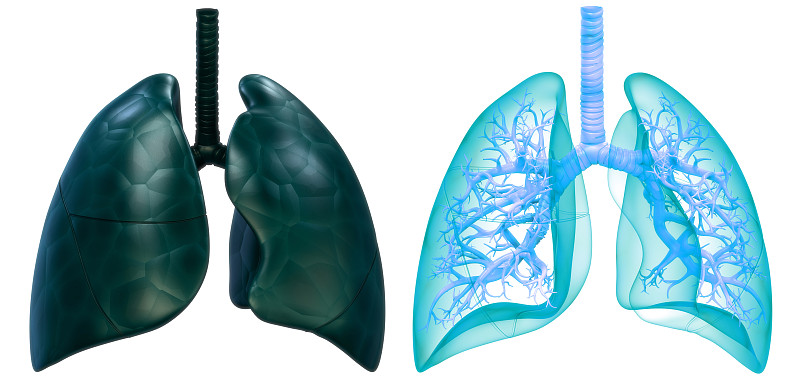

人体呼吸系统肺解剖详情

JPG